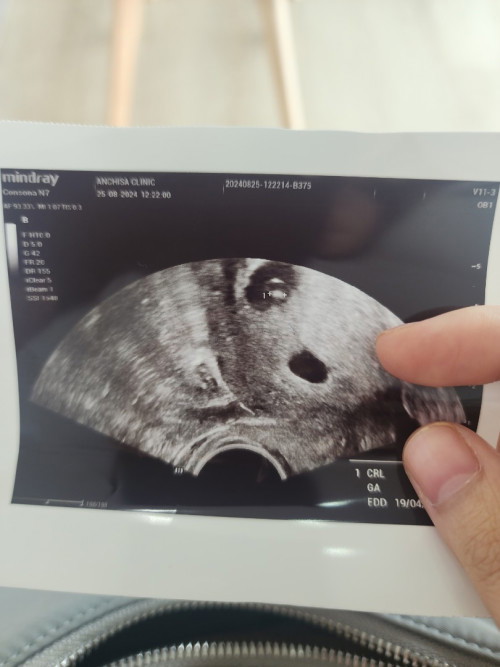

ตั้งครรภ์ 6 สัปดาห์ค่ะ คุณหมอนัดซาวเจอถุงตั้งครรภ์ แต่ยังไม่เห็นตัวเด็ก คุณหมอบอกว่าเห็นถุงไข่แดงข้างใน ตอนนี้แม่เครียดกลัวเปนท้องลม ตอนแม่ๆ6สัปดาห์ ซาวเปนแบบไหนกันบ้างคะ

ของเราซาวด์ตอน6วีค เจอถุงตั้งครรภ์กับตัวอ่อน เราซาวด์ช่องคลอดค่ะ เห็นแน่นอนคุณหมอบอกค่ะ